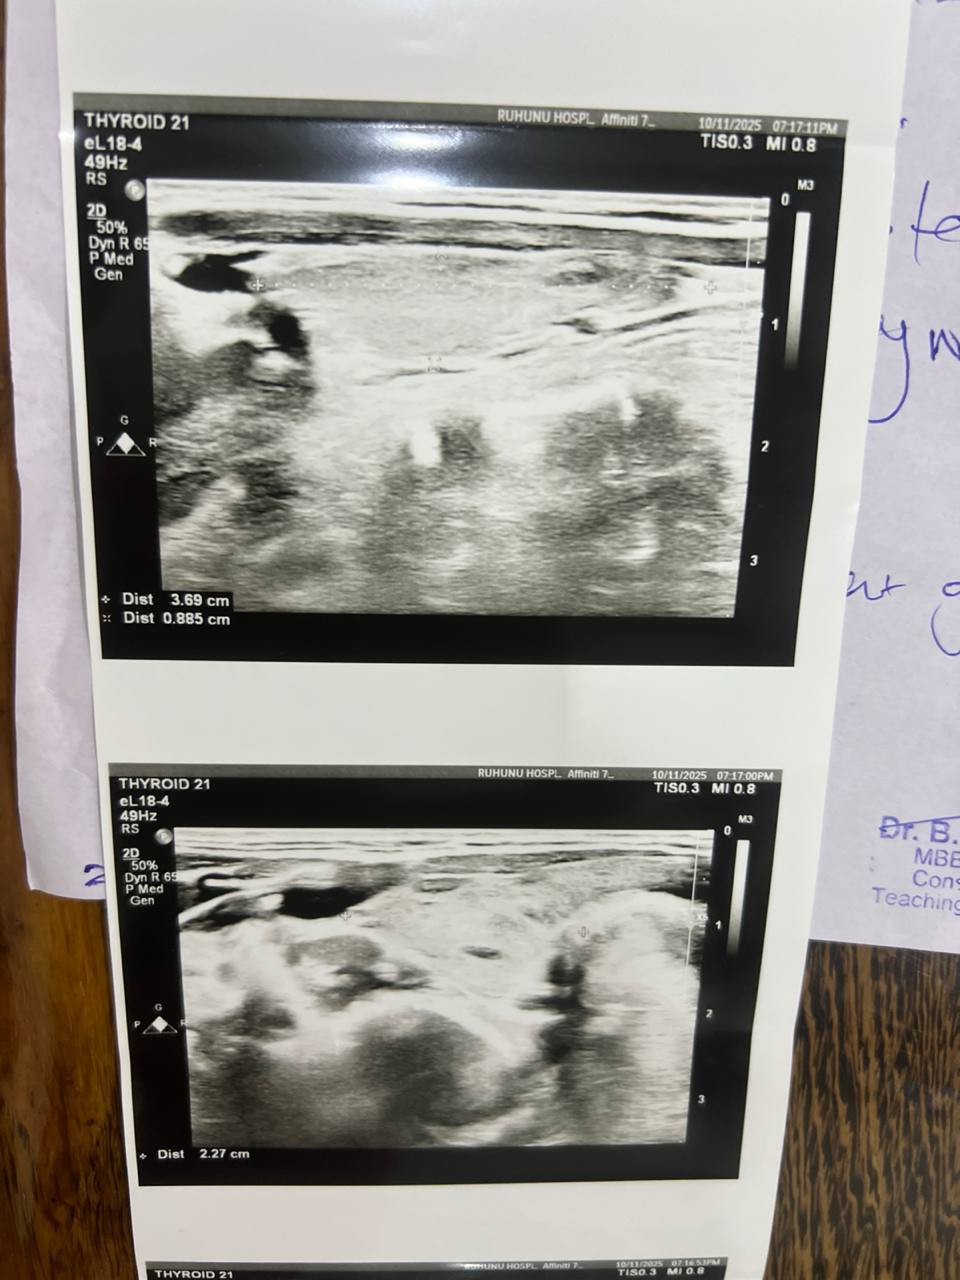

Недавно я сделала УЗИ щитовидной железы:

Незначительное увеличение правой доли щитовидной железы.

Правая доля: 5 см × 1,4 см × 2,2 см

Левая доля: 3,6 см × 0,8 см × 2 см

Очаговых узлов и зоба нет.

Узи расшифровал обычный врач не эндокринолог, вы разбраетесь в снимках? Скажите, подалуйста, на них соответствует картина действительности 65985464.jpg

| Vitaly, здравствуйте! Можете не сомневаться в точности диагноза аутоиммунного тиреоидита, он подтверждается у вас всеми признаками: УЗИ картиной, повышенным титром антител против щитовидной железы, наличием гипофункции - гипотиреоза. Когда начнете лечение гипотиреоза, нужен контроль ТТГ и Т4св через 2-3 мес. для коррекции дозы. Когда доза будет подобрана правильно, можно будет контролировать только ТТГ (TSH) 1 раз в 6 мес. Контролировать и вообще проверять в дальнейшем антитела не требуется, особенно TSH receptor antibodies У вас есть недостаточность витамина Д и железодефицит, рекомендую их устранить приемом витамина Д (в зависимости от веса, не менее 5-7000 IU витамина Д в сутки на 2 мес, затем перейти на поддерживающие дозы - 2000 -2500 IU длительно). И также нужен препарат железа. Контроль ферритина через 1,5-2 мес (цель - выше 50-60). Контроль витамина Д не нужен, анализ не является достоверно точным. Вы можете совместно принимать и левотироксин (гормон), и витамин Д, железо, селен, омега, но не комбинировать одновременно данные БАДы с тироксином (он отдельно принимается, строго натощак утром). Магний можно пропить позже, по окончании приема железа, они мешают усвоению друг друга. Кальций у вас в норме. Изолированное повышение MPV само по себе ни о чем не говорит, если остальные индексы тромбоцитов в норме.